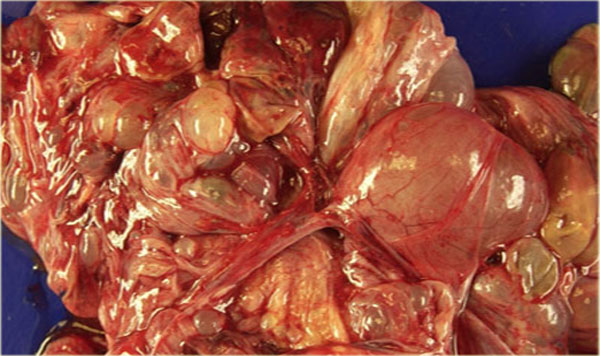

Specimen of the mucinous cystadenocarcinoma Specimen of the mucinous cystadenocarcinoma

The thin, relatively avascular septae, the absence of frank solid components, the absence of ascites and peritoneal carcinomatosis and the absence of invasion, suggest a lesion of low malignant potential (LMP).

Note however, that this diagnosis can not be made on imaging findings alone.

Especially the absence of invasion in ovarian stroma cannot be judged reliably on imaging.